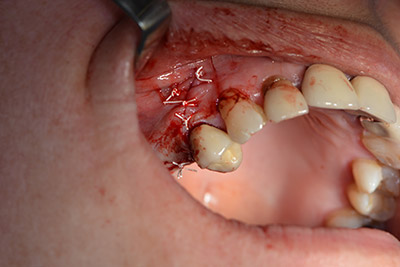

Dunque, l'impianto viene posizionato e l'osso ricostruito. In questo caso, considerate le dimensioni della regione di accrescimento, i microframmenti dell'osso autologo (raccolti con un'apposita cannula di aspirazione in seguito alla perforazione dell'impianto 16 e della fenestrazione 14) vengono combinati con dei materiali di riempimento dell'osso.

Una membrana riassorbibile viene usata come barriera in direzione buccale per contenere l'accrescimento. Infine, vengono applicate suture resistenti alla saliva (da fig. 15 a 19).

Accrescimento con osso autologo

Impianto

Implantologia

sutura della ferita a prova di saliva